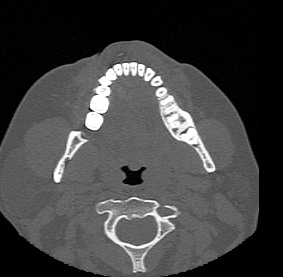

Одним из методов диагностики заболеваний носоглоточной области является мультиспиральная компьютерная томография. КТ носоглотки назначают при подозрении на рост новообразований, в случае хронического воспаления, при врожденных аномалиях строения носа и прилегающих к нему придаточных пазух.

Методика предусматривает использование рентгеновского излучения. Благодаря различной способности тканей поглощать рентгеновские лучи и последующей цифровой обработке полученных данных, удается получить изображения исследуемой зоны в мельчайших подробностях.

В медицинских центрах «Доступная медицина» сканирование носоглотки выполняется на современных мультиспиральных компьютерных томографах экспертного класса TOSHIBA AQUILION. Модификации данных аппаратов снабжены увеличенным количеством высокочувствительных детекторов, которые производят послойное сканирование, делая одномоментно от 64 до 128 срезов анатомической зоны. Это позволяет проводить исследование за несколько секунд. Такая быстрота выполнения исследования обеспечивает минимальную дозу рентгеновского облучения для пациента.

Инновационные цифровые приложения томографов позволяют получить снимки высокого качества и детализации, а также создать трехмерные реконструкции анатомической зоны исследования, что дает возможность рассмотреть пространственное расположение органов и патологических образований.

Мультиспиральная компьютерная томография позволяет выявить практически все заболевания ЛОР-органов и, в частности, носоглоточной области. С помощью КТ носоглотки можно диагностировать:

- доброкачественные и злокачественные опухоли носоглотки, придаточных пазух носа, костей лицевого черепа с определением их размеров и точной локализации, поражение регионарных лимфоузлов;

- аномалии развития носовой перегородки и области носоглотки.